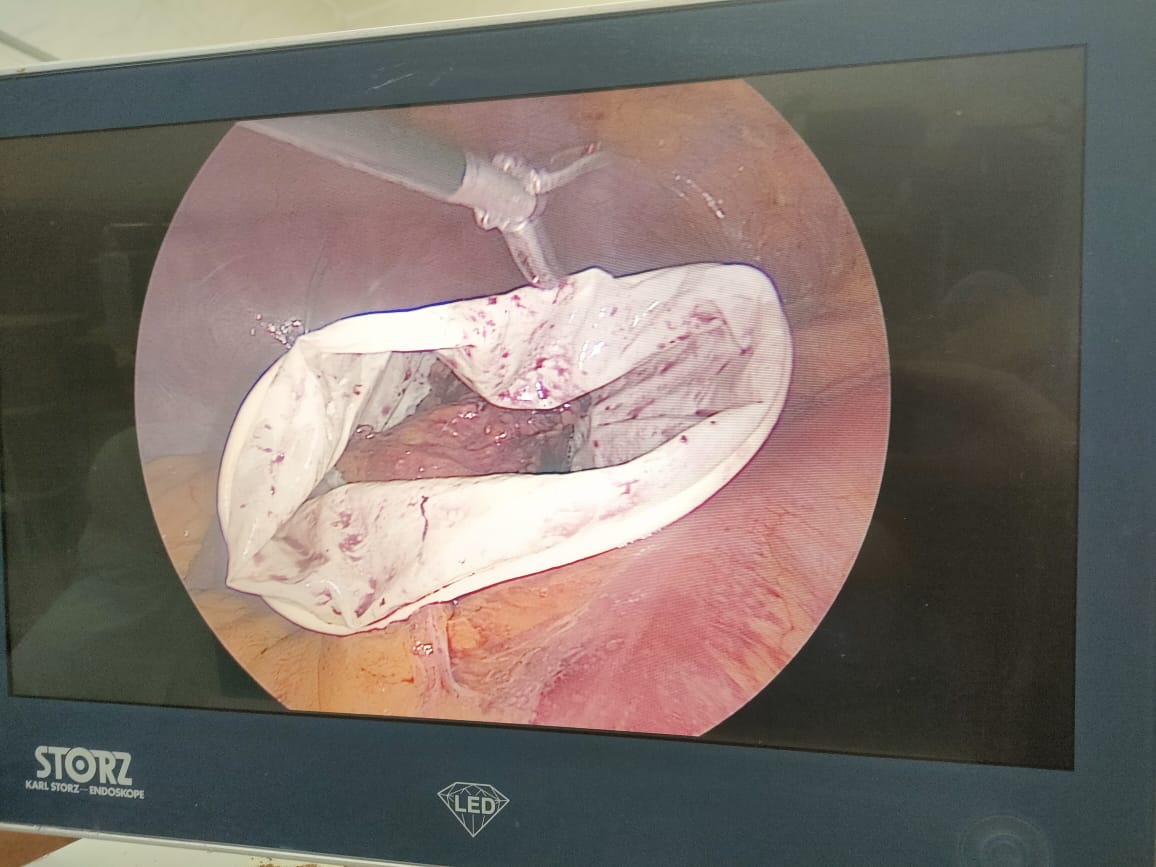

وأضاف سليمان: تم إجراء الجراحة للمريض باستخدام تقنية المنظار الجراحى، وهى أحدث التقنيات العلاجية المستخدمة في هذا المجال، حيث تم استئصال الورم من الغدة الكظرية اليسرى بجانب استئصال المرارة، لافتا إلى استقرار الحالة الصحية للمريض وخروجه من المستشفى بعد متابعة حالته الصحية.